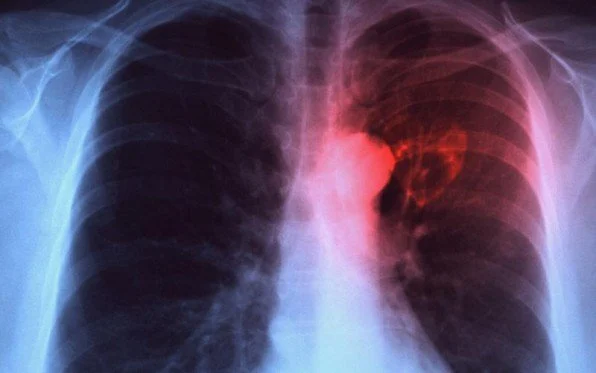

चार सय ३१ जनामा फोक्सोसम्बन्धी क्षयरोग देखापरेको छभने एक सय ३९ मा अन्य क्षयरोग देखिएको फोकल पर्सन दासले बताए । उनका अनुसार एचआइभी सङ्क्रमित नौजनामा क्षयरोग देखिएको छ । औषधि प्रतिरोधी क्षयरोगका बिरामी सातजना रहेका स्वास्थ्य कार्यालय झापाले जनाएको छ ।

फोकल पर्सन दासले सङ्क्रमण पत्ता लागेका तीन प्रतिशत बिरामीको मृत्यु भएको भन्दै मृत्युु हुनेमा ३५ प्रतिशत महिला र ६५ प्रतिशत पुरुष रहेका जानकारी दिए । सङ्क्रमित बिरामीमध्ये आठ प्रतिशत १५ वर्षमुनिका बालबालिका रहेका छन् । करिब ७२ प्रतिशत बिरामी फोक्सो सङ्क्रमित छन् भने २८ प्रतिशत बिरामी फोक्सोबाहेक अन्य अङ्गहरुको सङ्क्रमित छन् ।

दुई हप्ताभन्दा बढी समय एकनासले खोकी लाग्नु, खोक्दा खकारमा रगत देखिनु, साँझपख ज्वरो तथा पसिना आउनु, खानामा रुचि कम हुनु, तौल कम हुनु क्षयरोगका प्रमुख लक्षण हुन् ।